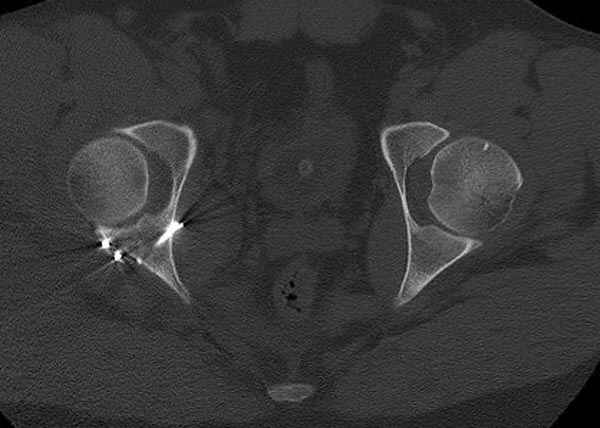

11:50 больной в послеоперационной, рентгенограмма N7, компьютерная томограмма в тот же день N8-10

7:30 начало операции, больной на спине, попытка репозиции после анестезии N3, укладка больного на боку, доступ Kocher- Langenbeck, состояние седалищнего нерва около 2.5см кровоподтек, через joistick головка бедра приподнята, освобовождение сустава, фрагмент заднего края более 3х4 см репонирован на свое место. После промывания

сустава, репозиция вывиха (N4), фиксация фрагмента 2.7(4) мм шурупами и допольнительно реконструктивной пластиной на 8 дырок, фиксация 3.5мм шурупами проксимально и дистально.